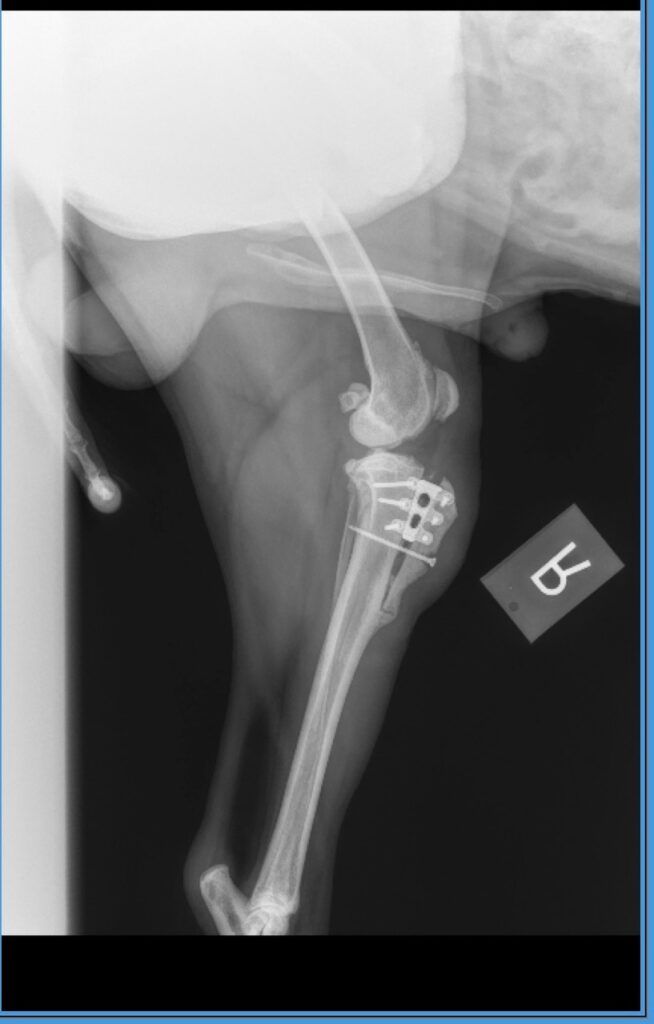

This was the hunt where Aspen tore ligaments in his knee in this crusted snow. The photo is of the last opportunity I had from over one of his points. Wouldn’t you know I missed a “gimme” shot like this(!)

Aspen’s surgically repaired knee still requires that he have close confinement and short lease walks only. It also took my photographer away from hunts while she tended to him.